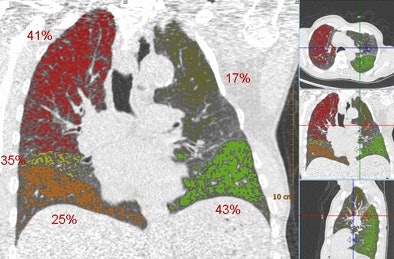

| Above, images from the expiration scan of a 65-year-old man with GOLD stage 3. The image shows increased density in some areas, common in expiration scans, but also regions that remain dark and are indicative of air trapping. Below, the overlay images from a single coronal section show that the left upper lobe is normal, while two lobes had emphysema and two had air trapping, indicating mixed-phenotype COPD. |